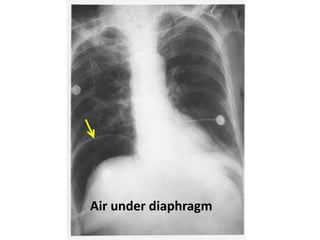

Air under the diaphragm : perforated viscus

Air under diaphragm